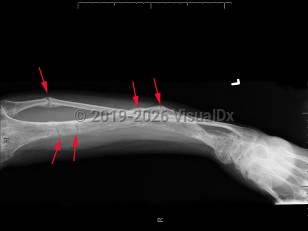

Clinical presentation is variable and typically presents after 18 months of age or when the pediatric patient begins to walk. Symptoms range from growth retardation and short stature to severe rickets or osteomalacia. Some patients have isolated hypophosphatemia detected on serologic testing. The typical presentation is a child with leg bowing and other bone deformities, pseudo-fractures, bone pain, and short stature. Rarely, a patient may present with tetany, dental enamel defects, and spine or pelvic rickets.

Familial hypophosphatemic rickets is a group of familial disorders characterized by hypophosphatemia and rickets as well as resistance to physiologic vitamin D repletion. The most common of these is X-linked hypophosphatemic rickets (XLH), in which an inactivating mutation leads to elevated serum fibroblast growth factor 23 (FGF23) levels, resulting in renal phosphate wasting. Sometimes the condition can arise from a spontaneous mutation.